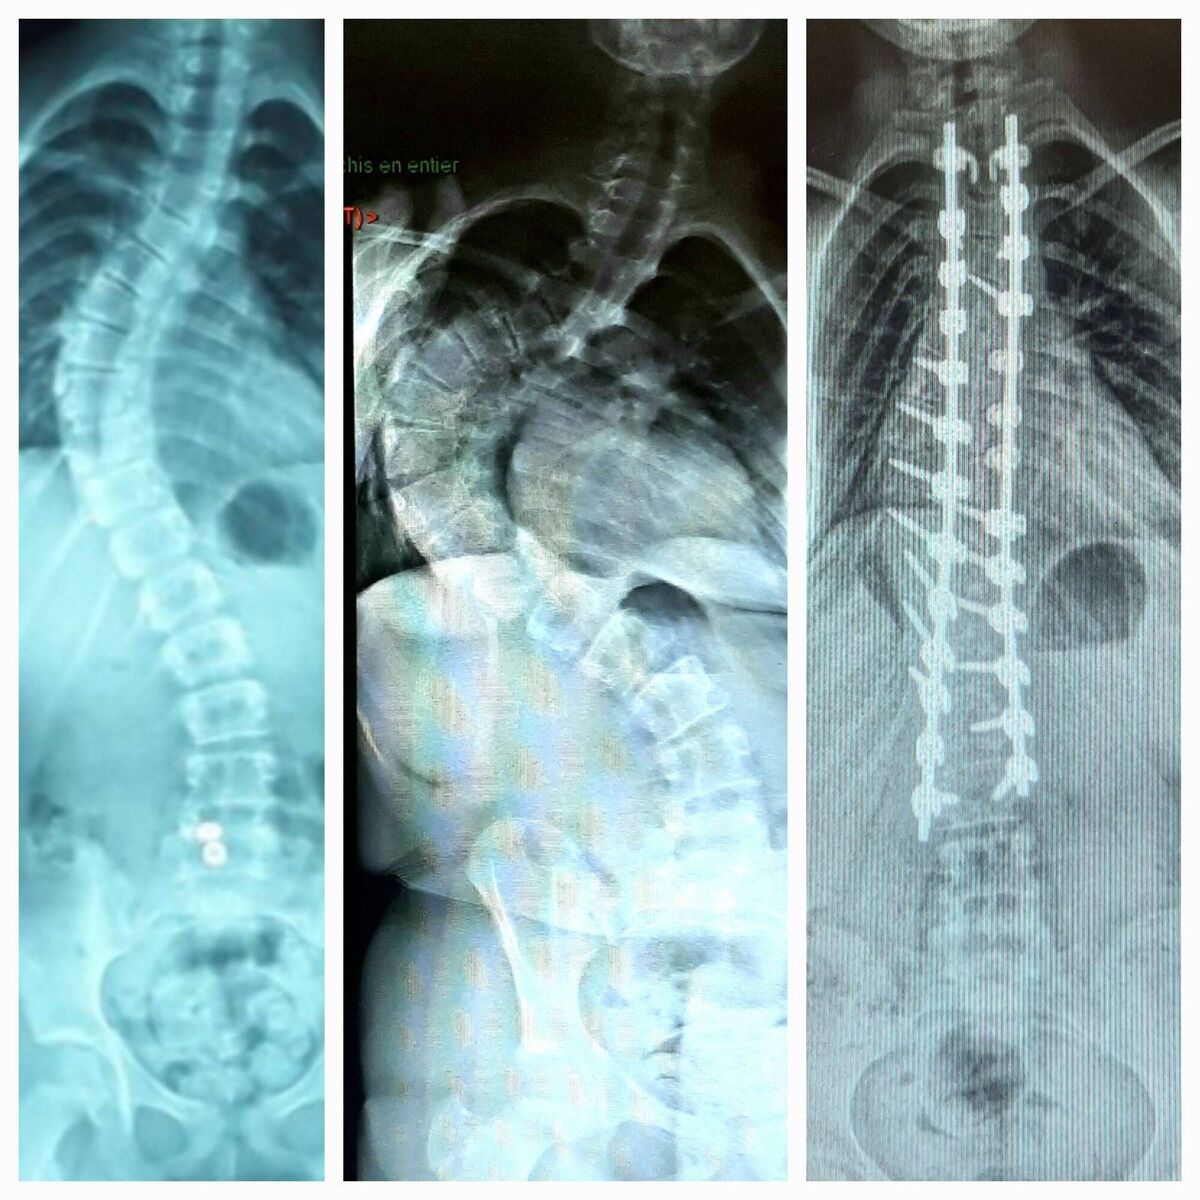

“We were thinking it was probably scoliosis, but we were not sure until he had an X-ray," said Dan.

But it was eight months later when they first met a consultant in Crumlin, by which time they had already been to Finland and Daithi had received care and further X-rays.

Within two months, the degree of curvature in Loanne’s spine reached 115 degrees deviation from 64 degrees when first diagnosed.

Ultimately, Shane said: “She had halo on February 2, 2022, and spinal fusion along with thoracoplasty — five ribs broken and reset — in March 2022.”